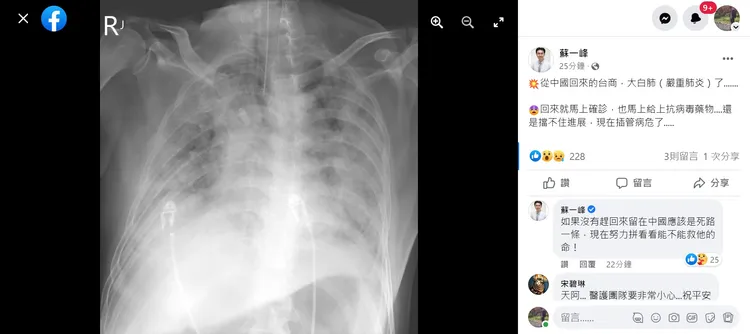

醫師蘇一峰6日在臉書發文,有一名剛從中國返台的60歲台商,回台後三天自己快篩驗出確診,從X光片顯示,患者已呈現嚴重肺炎的大白肺,他直言「如果沒有趕回來留在中國應該是死路一條」。

蘇一峰說,但病患確診後沒有第一時間就醫,等四、五天身體不舒服,才拿藥吃,之後給抗病毒藥物還是檔不住進展惡化,「現在插管病危了」,蘇一峰表示,現在努力拼看看能不能救他的命!並建議指揮中心,應該驗看看這一位的病毒株,看看是哪一種。

返台台商確診後呈現嚴重肺炎的大白肺。翻攝自蘇一峰臉書